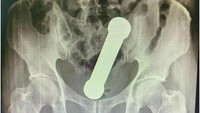

Seorang pria di Kalimantan Timur mengeluhkan sakit di alat kelaminnya. Ternyata, pria 48 tahun itu memasukkan sejumlah benda asing seperti kabel listrik, alat ekstraktor kartu SIM, hingga karet gelang. (Foto: Radiology Cases Reports)